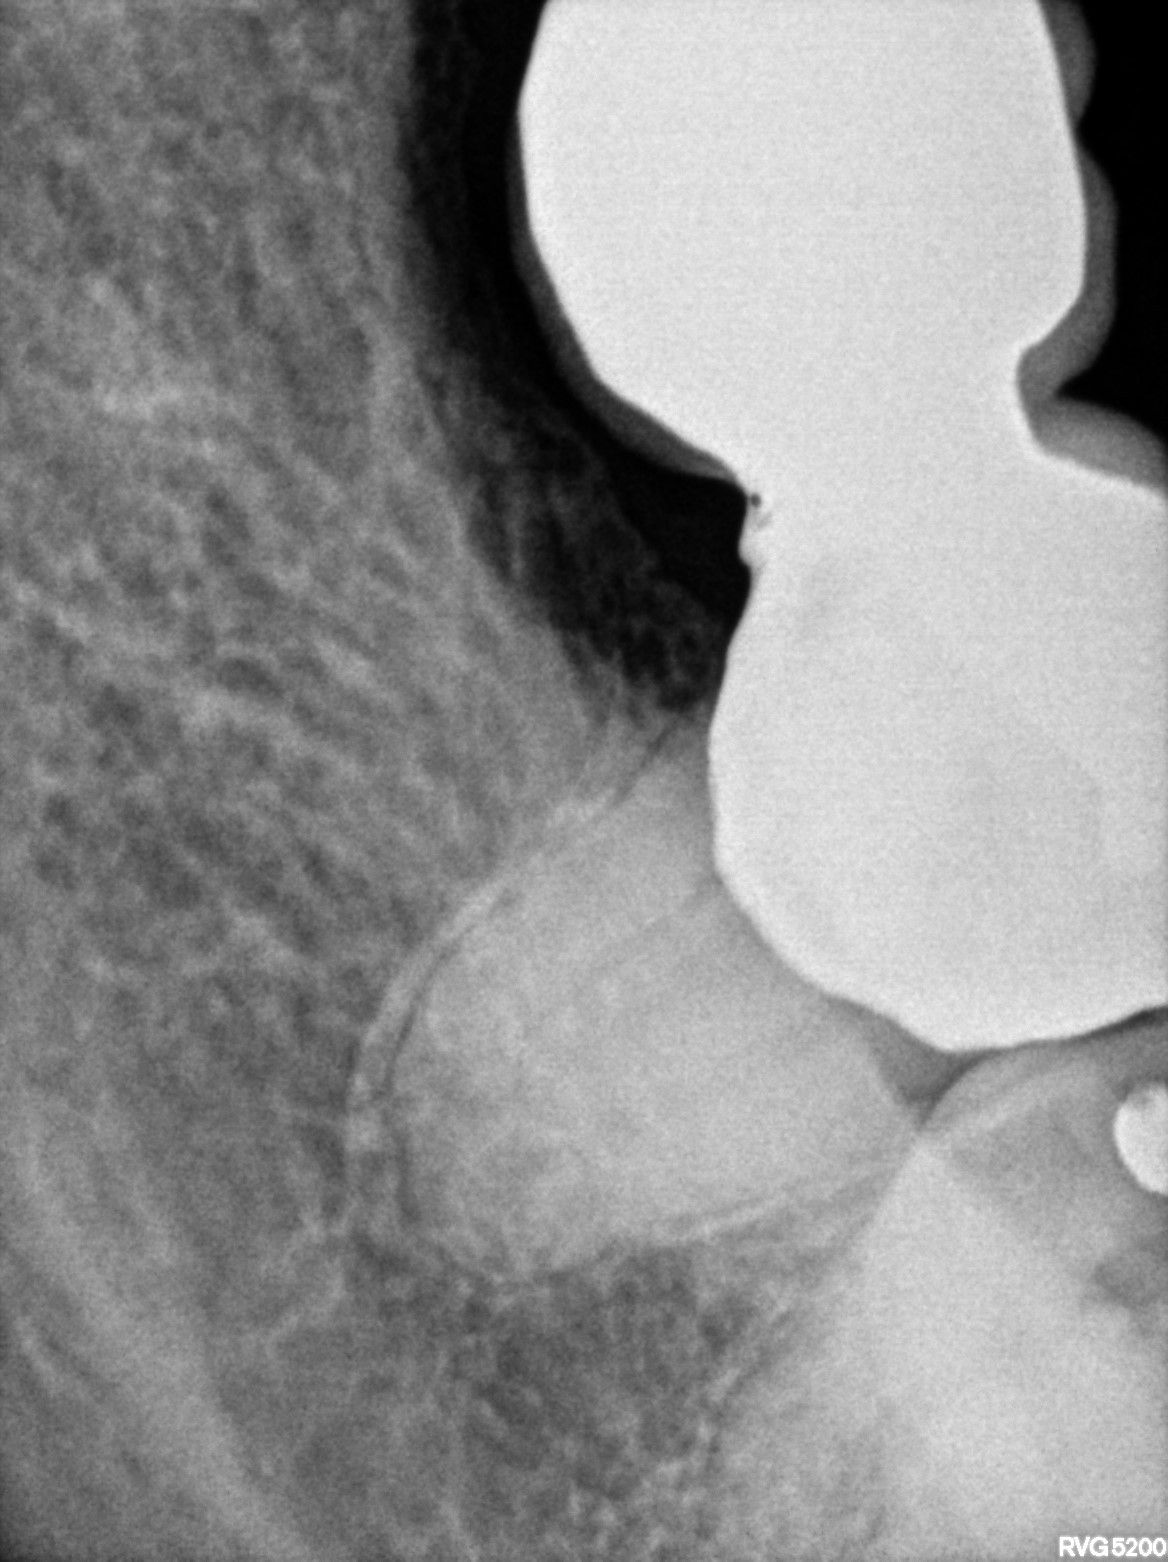

Dental Radiographs FHIR: DocumentReference · LOINC 24641-7

xray_1763362538_0.jpg

24641-7